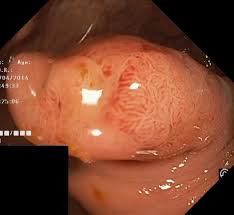

2) 선종성 용종

선종은 표면이 거칠고 돌기 형태를 보이거나 줄기처럼 올라온 폴립 형태를 띱니다. 크기가 클수록 암 위험이 높아지며, 1센티미터 이상이면 경계가 불규칙해 보이기도 합니다.

선종은 대장암의 원인이 되는 가장 흔한 전 단계 병변인 만큼 내시경의 숙련된 관찰과 조직검사가 매우 중요합니다.